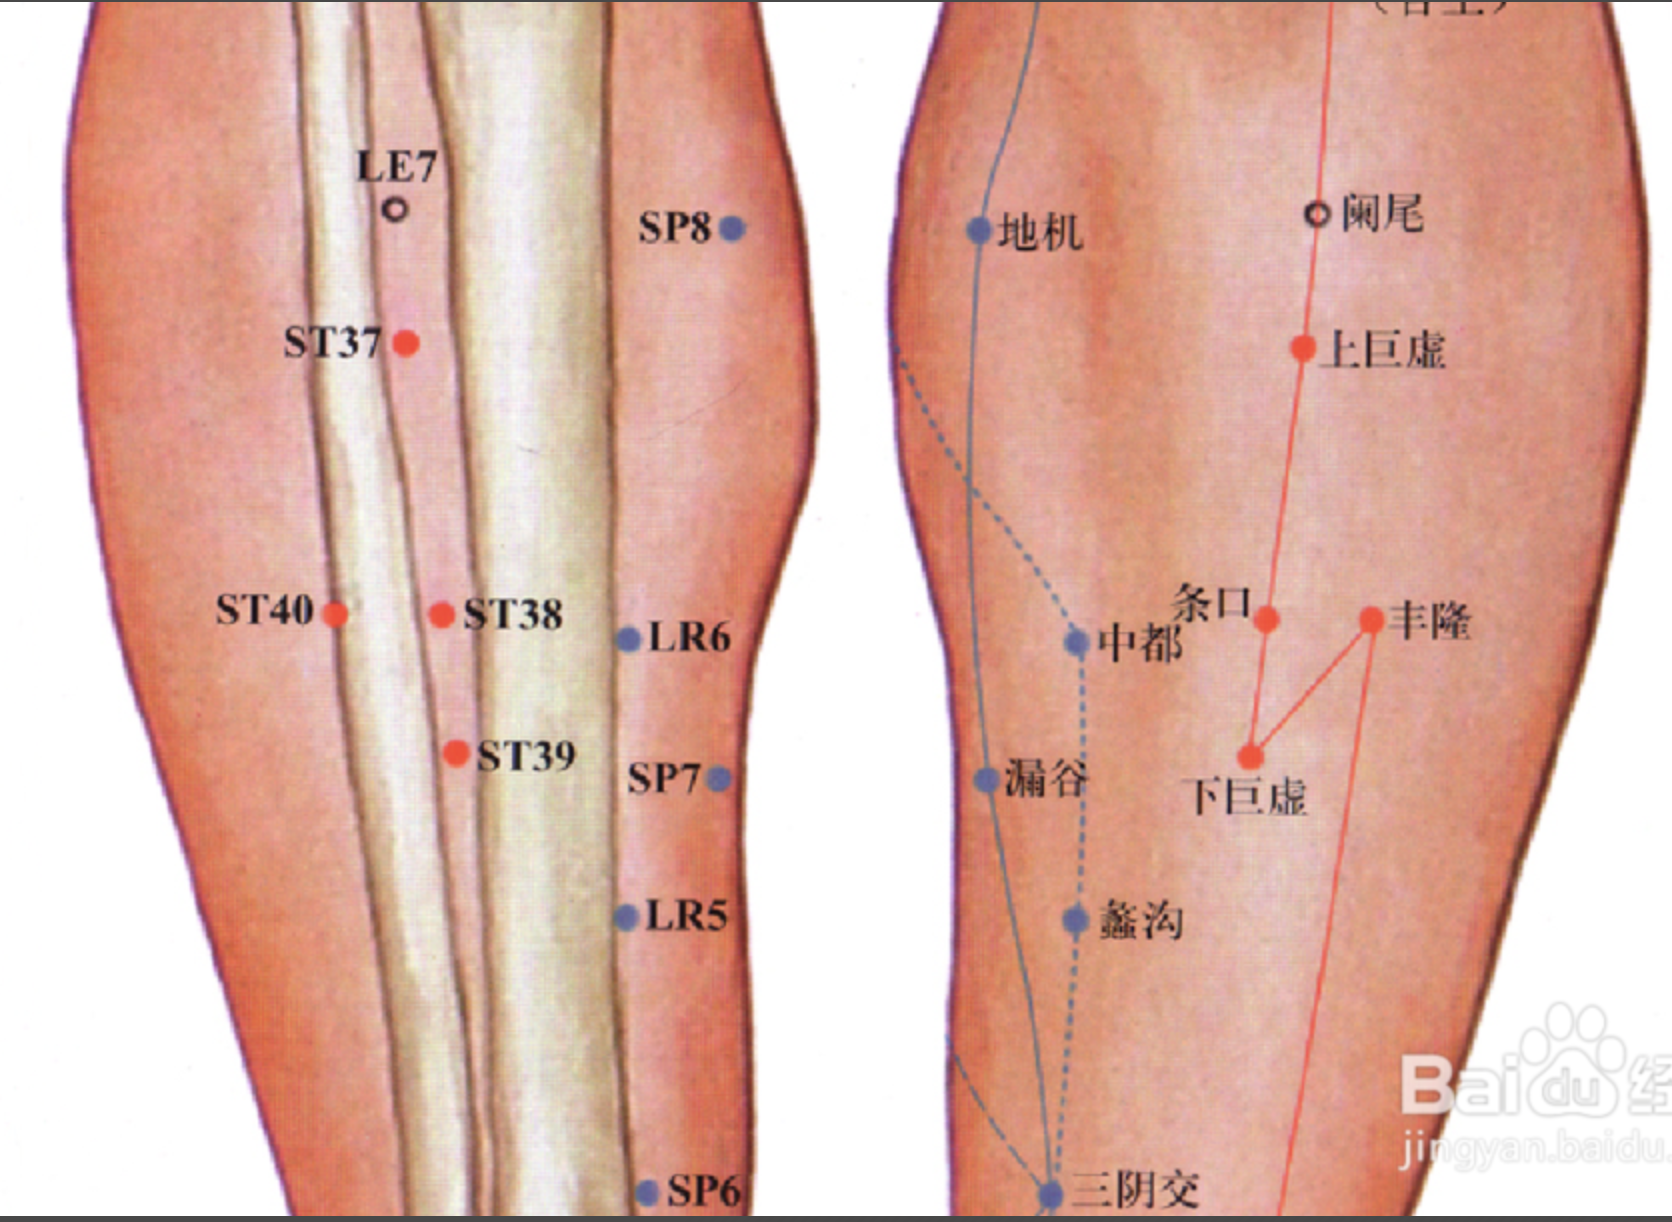

足三里

【定位】 在小腿前外侧,当犊(dú)鼻下 3 寸,距胫骨前嵴(jí)外 1 横指(中指)(图 10-21-4)。

丰隆

【定位】 在小腿前外侧,当外踝尖上 8 寸,条口外 1 寸,距胫骨前嵴外 2 横指(中指)(图 10-21-4)。

厉兑

【定位】 在足第 2 趾末节外侧,距趾甲角 0.1 寸。

【主治】 鼻衄,齿痛,咽喉肿痛,腹胀,热病,多梦,癫狂。

【配伍】 配内关、神门治多梦。

【刺灸法】 浅刺 0.1 寸。

【附注】 足阳明经所出为“井”。